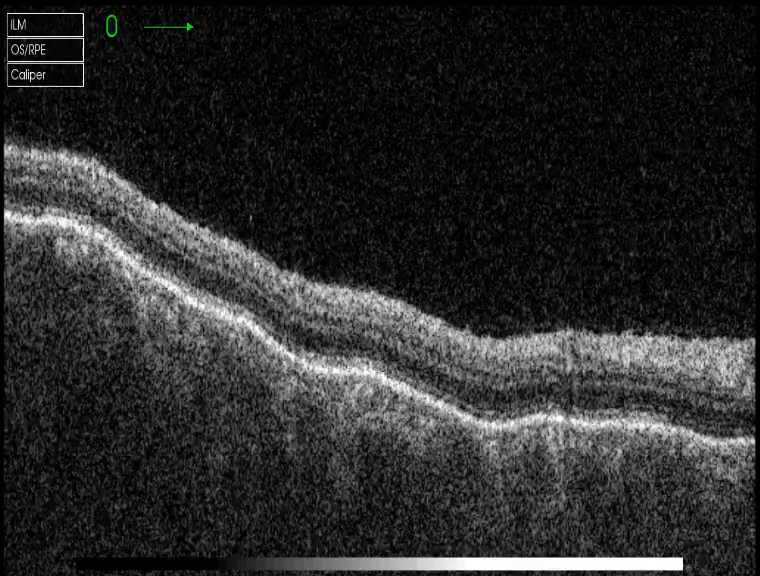

黄斑OCT:右眼明显脉络膜水肿增厚并可见RPE明显波浪样起伏,后极椭圆体带模糊消失,并 可见局限浆液性视网膜神经感觉层浅脱离,未见视网膜水肿增厚,未见明显黄斑区视网膜表 面新生血管样高反射信号,OCTA也未见新生血管信号;左眼视网膜平坦无起伏,网膜、脉络 膜大致可,黄斑区未见视网膜神经感觉层浅脱离,未见黄斑区网膜水肿,未见明确视网膜新 生血管样病灶。OCTA双眼未见明显脉络膜新生血管样病灶,但双眼可见明显后极广泛多发脉络膜毛细血管低信号斑点。 双眼B超:右眼球壁厚度明显增厚,后极球壁厚度约3mm,未见T形征,左眼后极B超未见明显 异常。

右OCT